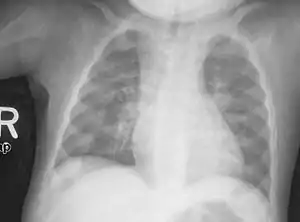

An X-ray or radiograph of an advanced patient with rickets tends to present in a classic way: the bowed legs (outward curve of long bone of the legs) and a deformed chest. Changes in the skull also occur causing a distinctive "square headed" appearance known as "caput quadratum".[14] These deformities persist into adult life if not treated. Long-term consequences include permanent curvatures or disfiguration of the long bones, and a curved back.[15]

- Radiography typically show widening of the zones of provisional calcification of the metaphyses secondary to unmineralized osteoid. Cupping, fraying, and splaying of metaphyses typically appears with growth and continued weight bearing.[40] These changes are seen predominantly at sites of rapid growth, including the proximal humerus, distal radius, distal femur and both the proximal and the distal tibia. Therefore, a skeletal survey for rickets can be accomplished with anteroposterior radiographs of the knees, wrists, and ankles.[40]